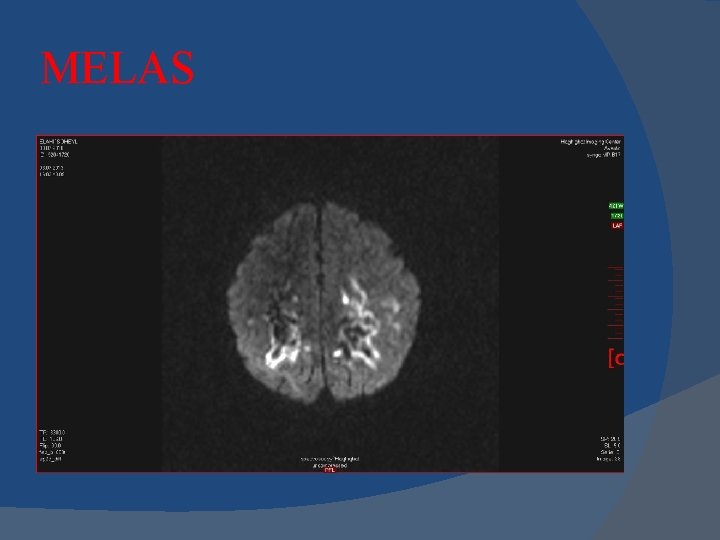

MELAS Mitochondrial myopathy, encephalopathy, lactic acidosis, and stroke-like episodes (MELAS)

MELAS Imaging Stroke-like cortical lesions crossing vascular territories , Posterior location most common "Shifting spread" (appearance, disappearance, reappearance elsewhere) is classic Lactate (Lac) "doublet" at 1. 3 ppm in 60 -65% MRS Basal ganglia (BG) lesions and calcifications

MELAS